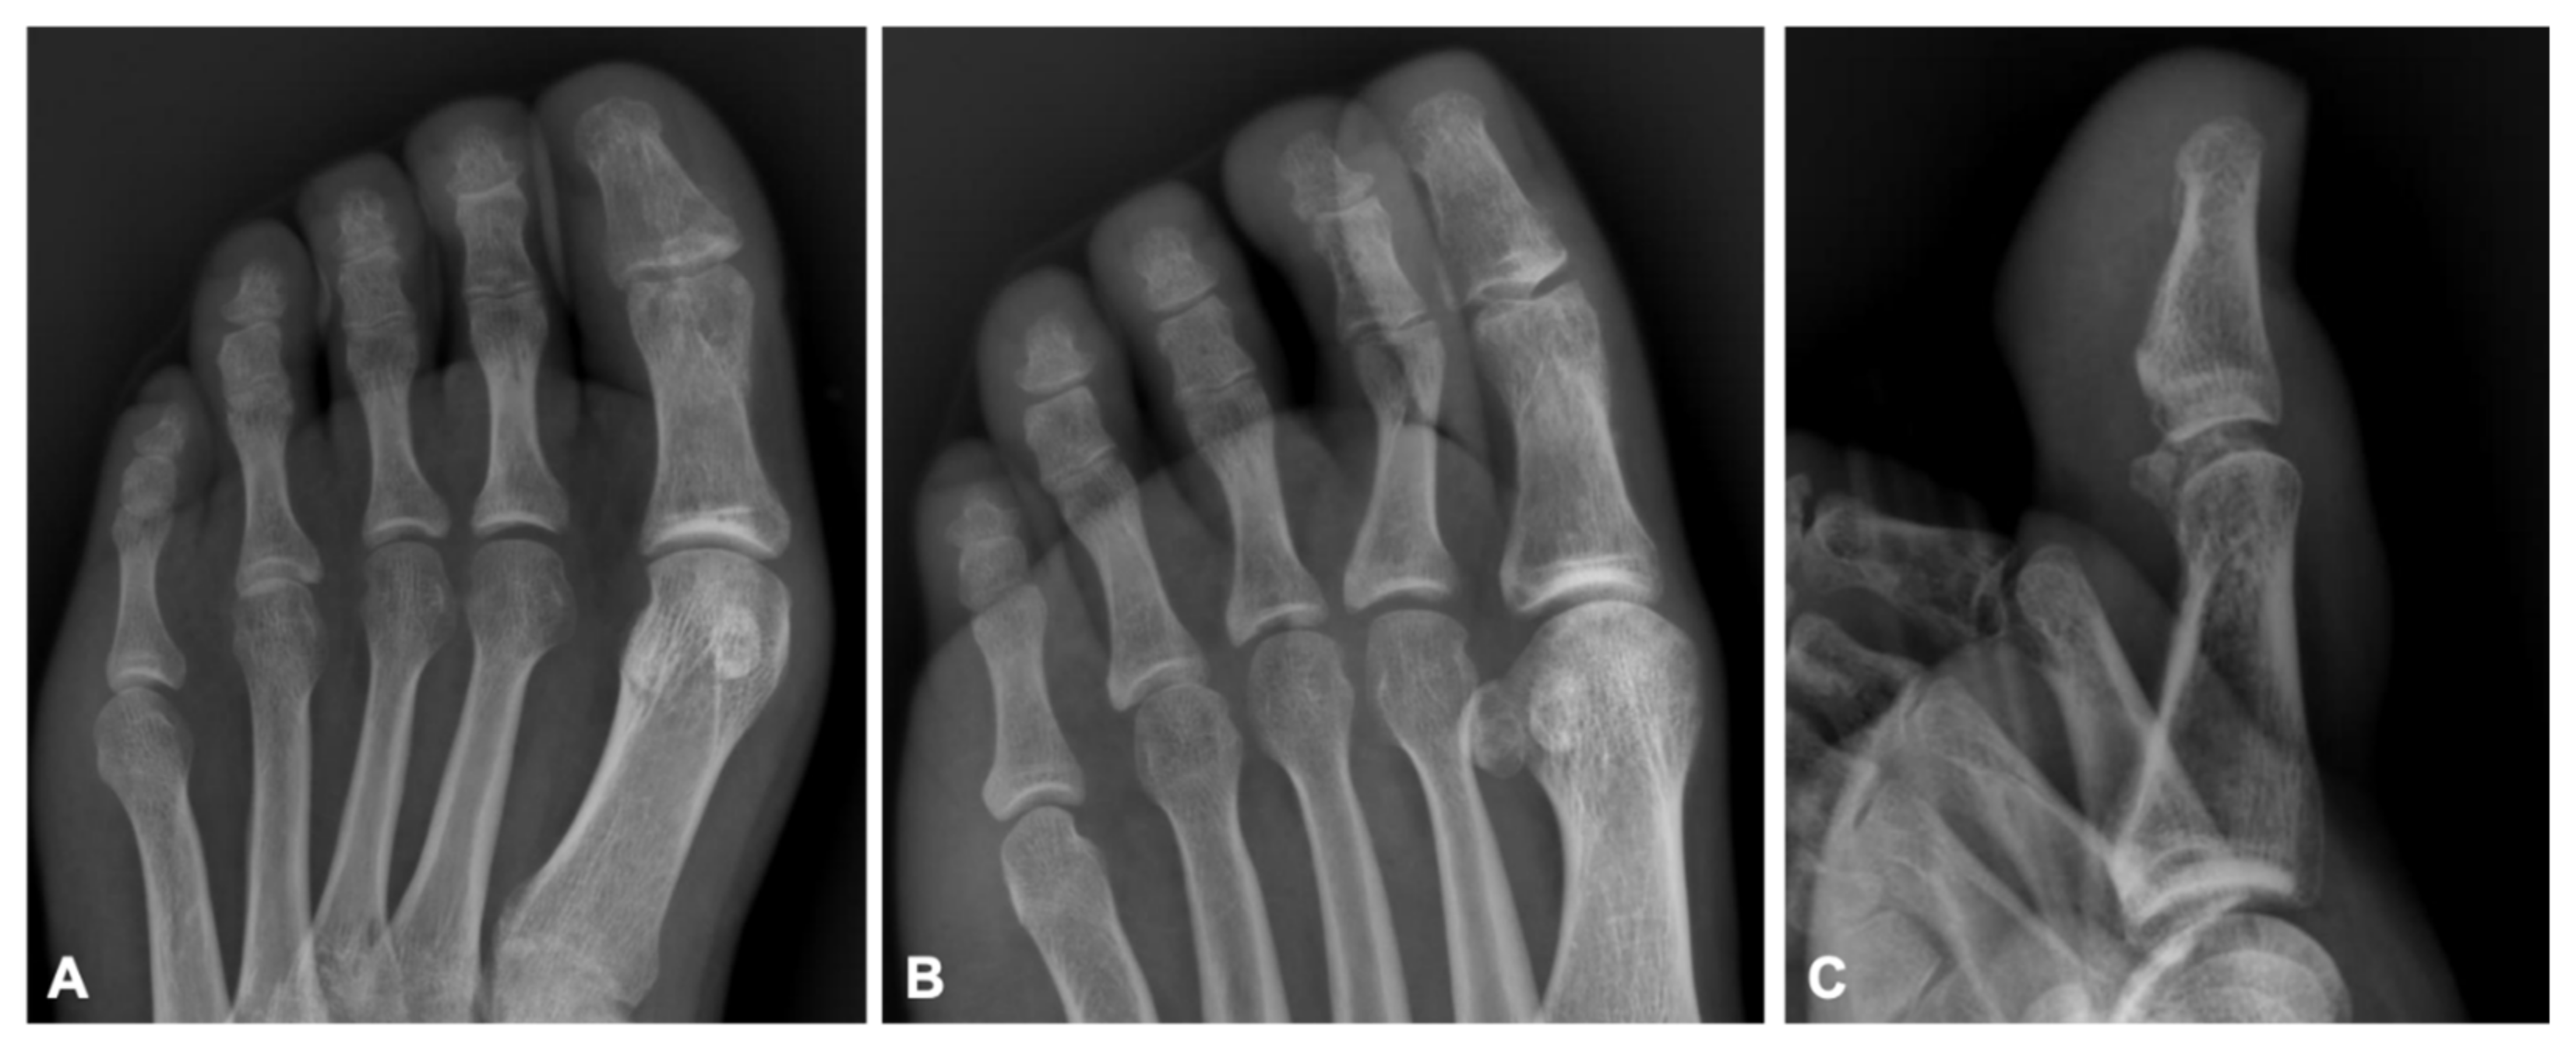

Initial management included debridement of the open fracture with sterile saline solution. The patient received appropriate antibiotic therapy and tetanus prophylaxis. The interphalangeal joint dislocation was reduced using manual maneuvers. Subsequently, a minimally invasive, cost-effective technique was implemented under local anesthesia using hypodermic needles:

A 21-gauge hypodermic needle was introduced through the medial aspect of the hallux at the distal fracture line of the proximal phalanx, intersecting the interphalangeal joint region. The needle was directed perpendicularly to the bone shaft, targeting the lateral cortex. It was positioned as not to penetrate the contralateral cortex, allowing intramedullary positioning to support fracture reduction and prevent inferior displacement of the oblique fracture.

An 18-gauge hypodermic needle was inserted through the distal tip of the hallux. It traversed the lateral edge of the proximal phalanx and extended toward the interphalangeal joint. The needle insertions were done blind without fluoroscopy by feeling the bone in the emergency department.

After needle placement and proper irrigation and debridement, the layers were sutured anatomically, and a short-leg splint in neutral position was applied. Control radiographs confirmed proper anatomical alignment of the fracture (

Figure 2). The patient was discharged and scheduled for weekly follow-ups after prescription of amoxicillin clavulanic acid 1 g twice a day. The hypodermic needles were removed during the fourth week in the outpatient clinic and passive range of motion exercises and weight bearing were begun gradually. After 6 weeks, radiographs showed fracture union (